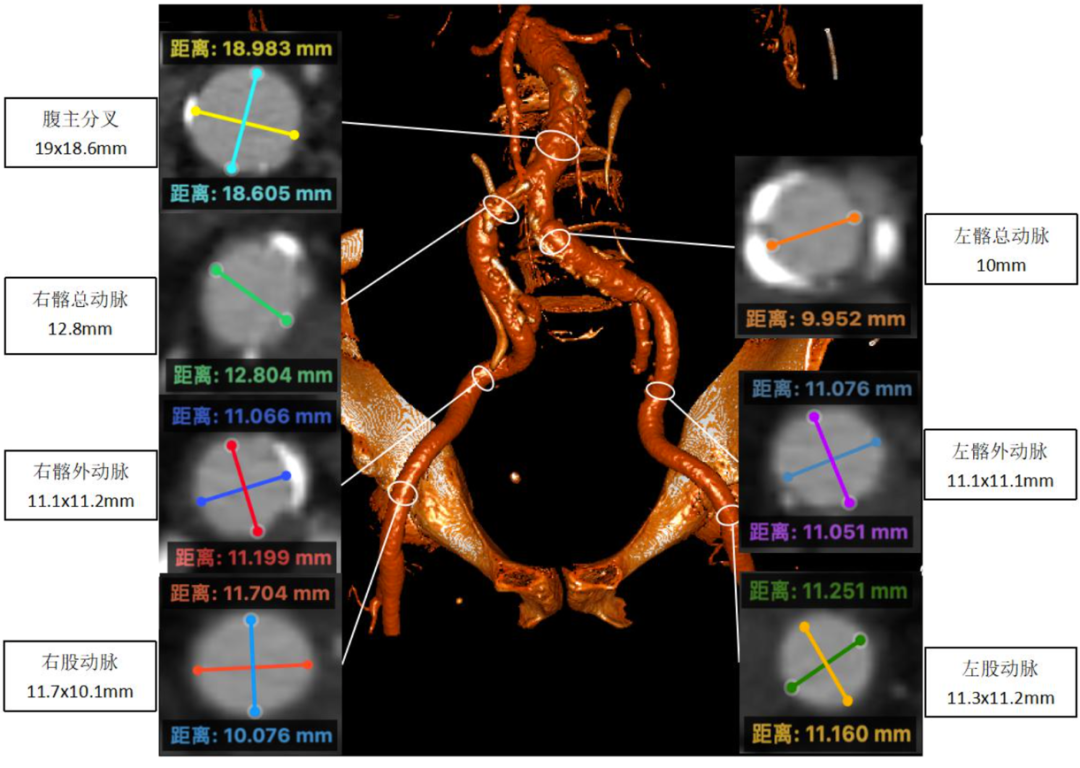

影像分析